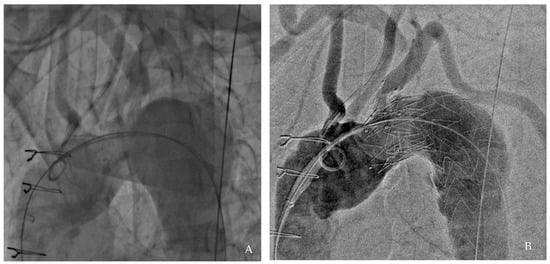

A final angiographic evaluation confirmed successful exclusion of the aneurysm and satisfactory perfusion of the supra-aortic vessels (Figure 2). The patient was discharged five days later on dual antiplatelet therapy (aspirin 100 mg and clopidogrel 75 mg) for three months, followed by lifelong aspirin monotherapy.

Figure 2. Angiographic results: pre-procedure (A) and post-procedure (B).